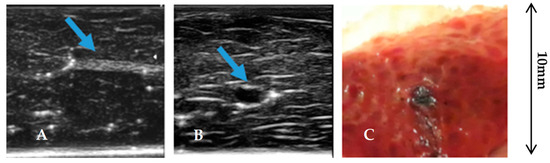

- Inclusion type II: Extended inclusions which filled almost entirely the channel produced by the syringe tip inserted into the tissue. They were obtained going on injecting a solution in the tissue while extracting the syringe;

- Inclusion Type III: Inclusions with the form of the open vessels (vein or artery) that we found in the dissection of the liver tissues and we utilized as a tube to be filled from the outside with the agar solution.